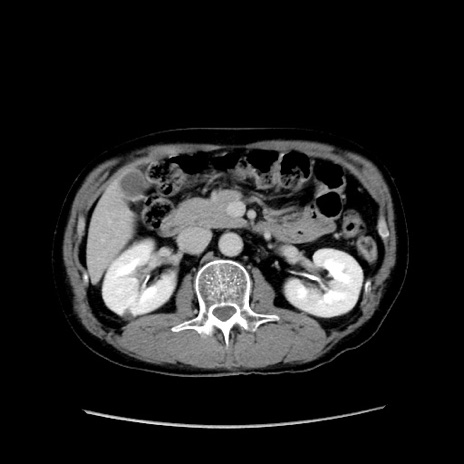

症例37(横断像)

【症例】40歳代 男性

【主訴】腹痛

【現病歴】4時間ほど前に電車に乗車中に臍部上より腹痛出現。徐々に増悪し起立困難となり、救急外来受診。生ものは数日食べていない。今朝お雑煮を食べた。

【身体所見】BT 36.8℃、BP 117/84mmHg、HR 91/min、SpO2 97%、苦悶様、腹部:臍上部広範囲圧痛あり、反跳痛±

【データ】WBC 8100、CRP 0.03